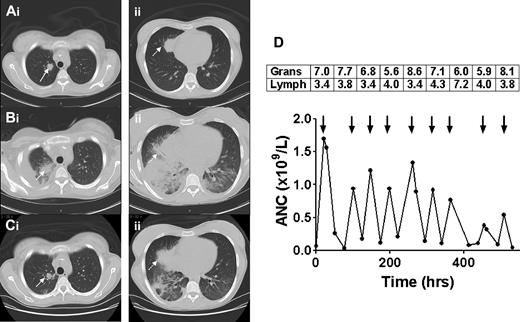

Sequential CT scans of the thorax and response to granulocyte transfusions. CT scan before granulocyte transfusions showed nodules in the right upper lobe (Ai, solid arrow, 2 cm) and right middle lobe (Aii, dotted arrow, 3.5 cm). CT after 4 transfusions of granulocytes revealed a new right pleural effusion, new right lower and middle lobe consolidation, and left lower lobe airspace disease, and enlargement of existing nodules (Bi-ii). CT after 5 additional granulocyte transfusions showed marked improvement in lung consolidations, accompanied by clinical resolution of fever, tachypnea, and hypoxia (Ci-ii). The granulocyte (× 1010) and lymphocyte (× 109) content of each of the 9 transfused granulocyte components (arrows) is shown in the boxes above the arrows, with the corresponding increment in ANC shown below the arrows (D). Mean granulocyte content was 6.9 × 1010 cells per product.

The mean posttransfusion ANC increment was 0.92 × 109/L during the first 7 granulocyte transfusions but diminished with the last 2 transfusions (Figure 1D). Although the patient had received approximately 100 leuko-reduced plateletpheresis and 200 leuko-reduced red cell concentrates during the course of her illness, neither class I nor class II HLA antibodies were detectable before granulocyte transfusion. A repeat HLA antibody screen performed 3 weeks after the first granulocyte transfusion revealed antibodies directed against both MHC class I (A25, B8, B45) and class II (DQ2, DQ4, DQ7, DQ8, DQ9, DR7) antigens. Unfortunately, the HLA type of the haploidentical sibling donor whose CD34+ cells had been collected and cryopreserved included DQB1*0302, which is the target of the anti-DQ8 antibody. HLA typing of the 9 granulocyte donors revealed that the first donor had the DQB1*0302 allele, which was probably responsible for the alloimmunization.

Fever, chills, and respiratory compromise are more likely to occur in the presence of recipient HLA alloantibodies.9 Granulocyte concentrates contain not only large numbers of granulocytes (expressing class I HLA antigens) but also substantial numbers of lymphocytes (expressing class II), thus providing ample antigenic stimulus (Figure 1D). A retrospective review at our center demonstrated that 17% of SAA patients developed HLA antibodies during the course of granulocyte transfusion therapy and that patients with detectable HLA antibodies had lower posttransfusion white cell increments.1 Ideally, donor-recipient pairs should be HLA matched; however, because the donor pool is limited, this is impossible in practice. Serologic screening for class I and class II HLA antibodies is recommended before initiating a course of granulocyte transfusions, at the end of the course, and whenever adverse pulmonary reactions or lack of the expected count increment occurs.